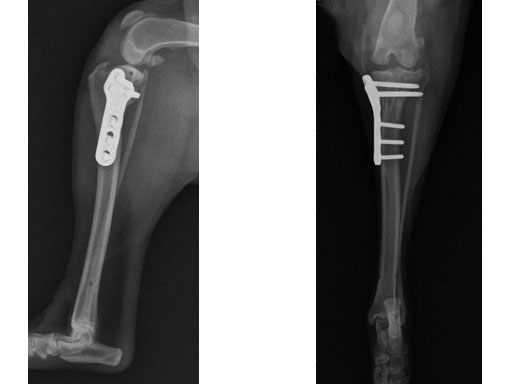

Case 2: Four-year-old English bulldog

(Case provided by Brian Beale, Houston, USA)

A four-year-old, female, spayed, 33 kg English bulldog had a CrCL tear and a medial patellar luxation. The small stature 3.5 mm TPLO plate was perfect for this dog due to the small profile of the bone and the need to use a heavier plate (3.5 vs a 2.7 mm). In the past, veterinary surgeons have been forced to either squeeze the standard TPLO 3.5 mm plate on the bone or use an undersized TPLO 2.7 mm plate. In this patient, the shorter and smaller profile head of the small stature TPLO 3.5 mm was perfect.